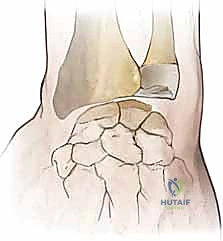

3. Creation of the Dorsal Capsular Flap

Now we focus on the dorsal capsule itself, which will form the basis of our capsulodesis.

- Flap Design: We need to create a robust, rectangular capsular flap. The dimensions are critical: approximately 25 mm long and 10 mm wide.

- Proximal Incision: We make a transverse capsular incision just proximal to the vascular dorsal carpal arch. This arch typically runs transversely across the dorsal aspect of the carpus. By staying proximal to it, we ensure the blood supply to our flap is preserved.

- Flap Elevation: Using a small periosteal elevator and careful sharp dissection with a #15 blade, we elevate the tissue in a distal-to-proximal direction. The key is to keep the flap thick and full-thickness, incorporating all layers of the dorsal capsule. We meticulously dissect it off the underlying carpal bones (scaphoid, lunate, capitate).